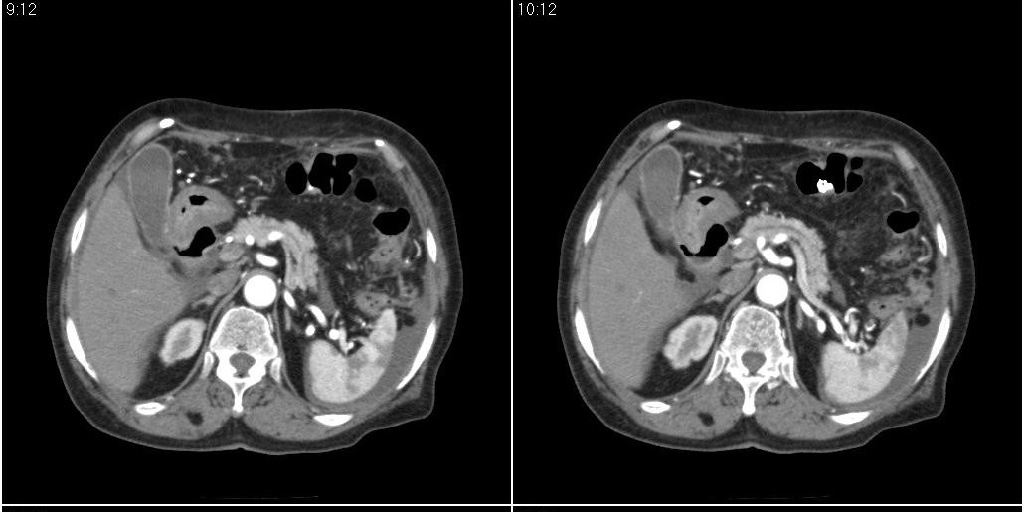

胆囊有问题么,是结石么?胆囊内异常密度平扫30hu左右,增强各期无变化。

胆囊内异常密度影增强各期无变化,考虑泥沙样结石。

胆囊内稍高密度影,无强化,胆囊壁增厚,周围见低密度影,右侧膈肌角及脾周水样密度,支持胆囊泥沙样结石,胆囊炎、胆囊窝积液,胸腹水。